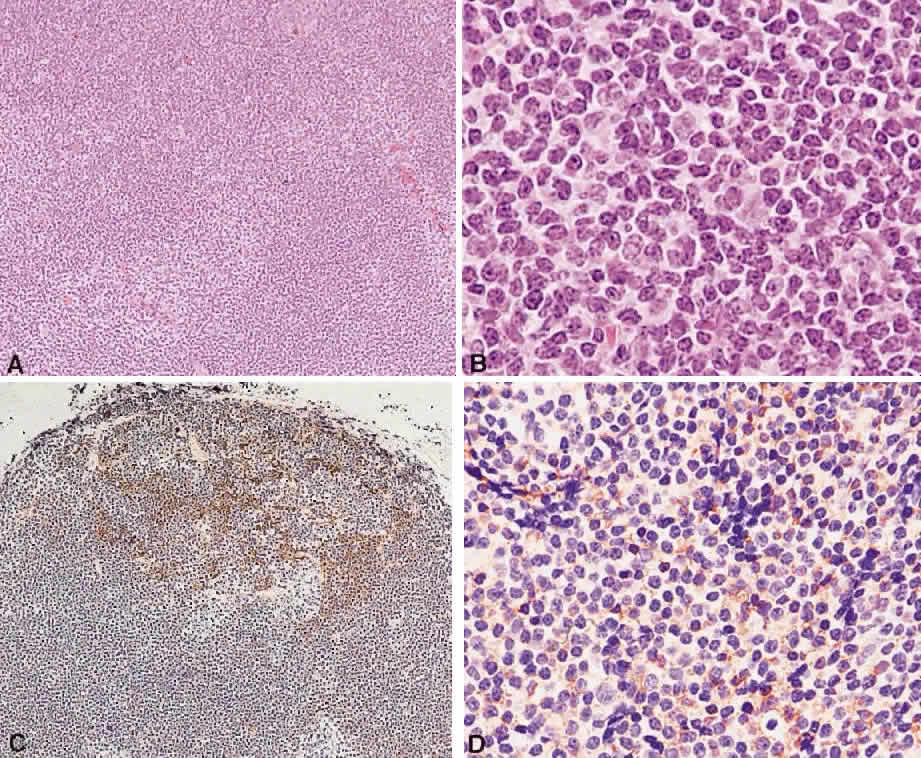

Numerous attempts have been made to classify lymphoid processes for clinical management and prediction of prognosis. Early classifications included only disease localized to the lymph node, which made classification of extranodal disease difficult and inaccurate. The Rappaport classification, first developed in 1956 and then modified in 1978, attempted to categorize lymphomas in two ways, first, using cytologic characteristics identified by conventional stains, and second, distinguishing between the follicular and diffuse growth pattern histologically38,39 (Table 3). The distinction of nodular, or follicular, and diffuse growth was considered useful because of the generally indolent nature of follicular growth, in which the tumor cell aggregates resemble germinal centers and disrupt the normal architecture of the node, compared with the appearance of diffuse growth, in which the lymph node is completely obliterated by a dense monotonous sheet of lymphocytes. In subsequent years, however, it was found that the descriptive growth pattern and cytogenetic characteristics of the Rappaport system did not predict prognosis reliably and were biologically inaccurate. The complexity of correlating degrees of differentiation, mitotic activity, and cytologic characteristics to prognosis have made lymphomas difficult to classify and have led to subsequent systems. The second system, proposed by Lukes-Collins in 1974, classifies lymphoma histologically according to its normal counterpart B-cell, T-cell, or null cell origin40,41 (see Table 3). Histologically, cells may appear small cleaved, large cleaved, small noncleaved, or large noncleaved, depending on the stage of B-cell arrest during normal transformation to immunoblast. Ninety percent of lymphomas are of B-cell origin, and the null cell also usually is of B-cell origin, although 10% may originate from T cells or histiocytes.42,43 Burkitt's lymphoma, the only lymphoma common in children, is a B-cell variant with a background of reactive histiocytes. As a result of histologic classification by Lukes-Collins, 76% of histiocytic lymphomas according to the Rappaport system were found to be not of histiocytic origin but of lymphocytic origin.40,44 The third system, the Working Formulation devised by the National Cancer Institute in 1982, attempted to predict prognosis by grouping lymphoma according to natural history, response to therapy, and overall survival.45 Three broad categories were established in terms of 5-year survival rates, the low-grade with a 50% to 70% survival rate, intermediate with 35% to 45%, and high grade with 23% to 32% (see Table 3). Orbital reactive hyperplasia, a relatively low-grade lesion, can be associated with systemic disease, whereas malignant or high-grade orbital lymphomas may be isolated findings. The Ann Arbor Staging Classification for Hodgkin's and non-Hodgkin's lymphomas was developed to stage disease based on systemic areas of involvement as a means of establishing a baseline for treating disease and following clinical progression46 (Table 4). Histologic classification, however, has been recognized as more useful than localization in the clinical management of nonHodgkin's lymphoma.47

While the Lukes-Collins and Working Formulation classifications were in wide use in the United States, the European literature made references to the Kiel and updated Kiel classifications, which led to disparities in classifying lymphoma. Another classification proposed by Jakobiec and coworkers was the most comprehensive classification available for orbital disease but failed to integrate systemic lymphoma, which is known to be associated in approximately half of cases.1 The most recent classification has made the system universal, comprehensive, and useful to interdisciplinary teams that characteristically manage patients with lymphoma. The International Lymphoma Study Group in 1994 developed the Revised European-American Lymphoma (REAL) classification (Table 5), which classifies lymphoid disease by the cell of origin into B-cell, T-cell, and natural killer cell lymphomas, leukemias, myeloma, and variants of Hodgkin's disease26 (Fig. 4). The identification of the putative benign progenitor cells has been inferred through the use of cell marker studies. The results of molecular genetic studies to identify immunoglobulin gene rearrangements and cytogenetic studies to detect chromosomal translocations in monoclonal proliferations have also been incorporated. A significant contribution of the REAL classification has been to incorporate primary extranodal lymphomas as recognizable and classifiable entities. As a result, new variants in this list include lymphoplasmacytic lymphoma, mantle cell lymphoma, marginal zone B-cell lymphoma, particularly mucosal-associated lymphoid tissue (MALT) lymphoma, subclasses of large cell lymphoma, and the natural killer cell lymphomas. Comparisons of the REAL classification to the Working Formulation and the Kiel classification are shown in Tables 6 and 7, respectively.48 The first series of 112 orbital lymphomas using the REAL classification reported the accuracy and utility of the system in classifying orbital lesions and predicting prognosis in combination with currently available immunophenotyping and immunocytogenetic studies.49 The REAL classification does not classify disease based on the degree of differentiation or clinical prognosis. However, a proposed prognostic scheme has been developed in accordance with the REAL classification28 (Table 8). In this text, tumor nomenclature adheres as strictly as possible to the REAL classification.